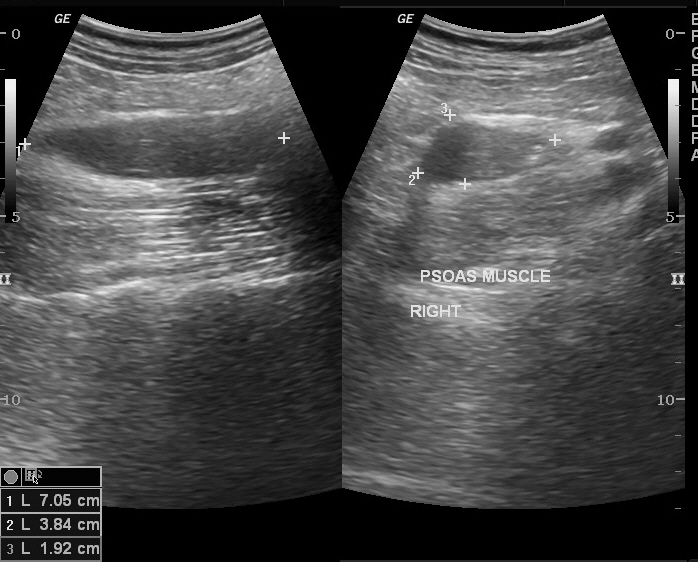

- УЗИ (ультразвуковое исследование органов брюшной полости). С помощью данной процедуры тоже возможно выявить гнойно-воспалительные процессы, затронувшие подвздошно-поясничную мышцу, а также их объем. Но в сравнении с вышеобозначенными это менее точный метод. Тем не менее звуковое обследование практически всегда позволяет найти источник распространения инфекции, масштабность проистекающего воспалительного процесса, а также оценить, насколько он затронул соседние органы и ткани.